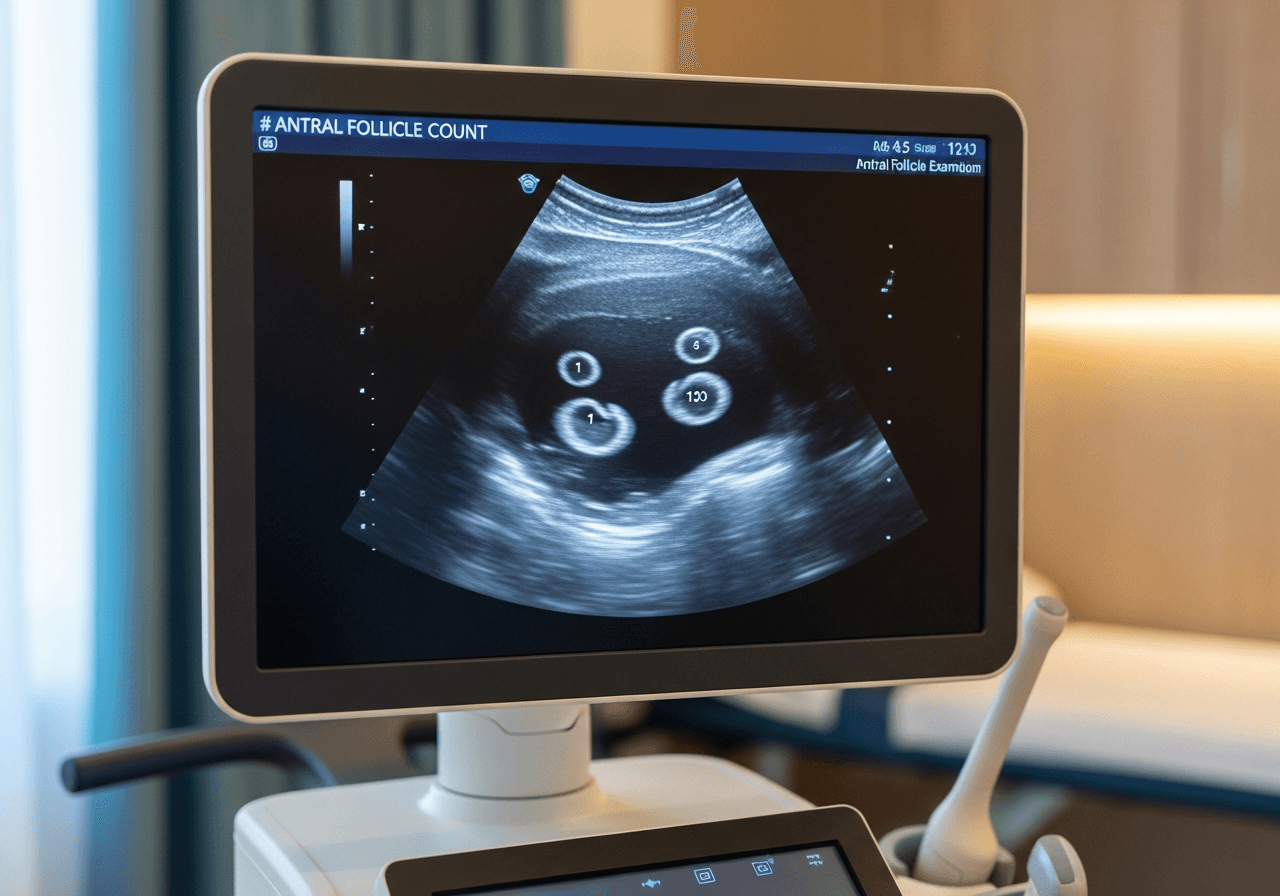

Le monitorage de l'ovulation consiste en plusieurs échographies pelviennes réalisées au cours d'un même cycle menstruel pour suivre l'évolution des follicules ovariens. Combiné aux dosages hormonaux, il permet de déterminer avec précision le moment de l'ovulation.

Le suivi commence généralement entre J2 et J5 du cycle (premier jour des règles = J1). Plusieurs échographies sont ensuite réalisées tous les 2-3 jours selon la croissance folliculaire observée.

- Échographie de base (J2-J5) : compte des follicules, aspect des ovaires

- Échographies de suivi : mesure des follicules dominants

Un follicule mature mesure environ 18-22 mm au moment de l'ovulation.

L'échographiste mesure les follicules et l'épaisseur de l'endomètre. Ces informations permettent de prédire l'ovulation et d'adapter la prise en charge. Un endomètre d'au moins 7-8 mm et d'aspect triple ligne est favorable à l'implantation.